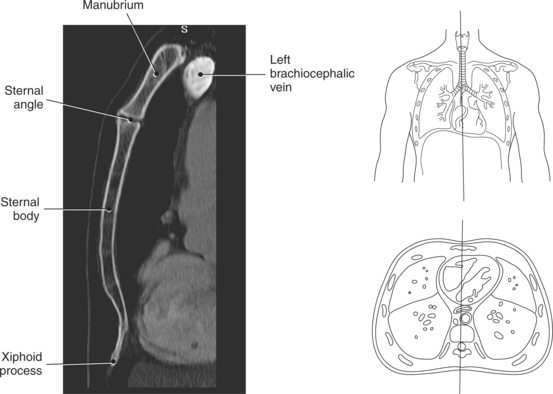

The bony thorax functions to protect the organs of the thorax and to aid in respiration. It consists of the thoracic vertebrae, sternum, ribs, and costal cartilages (Figure 6.2). The 12 thoracic vertebrae make up the posterior boundary of the thoracic cage. The anterior boundary is created by the sternum, located midline. The sternum has three components: manubrium, body, and xiphoid process (Figures 6.3 and 6.4). The triangular-shaped manubrium is the most superior portion and articulates with the first two pairs of ribs and the clavicles. It articulates with the clavicle at the clavicular notch to form the sternoclavicular joints (Figure 6.5). A common landmark, the jugular notch, is located on the superior border of the manubrium at approximately the level of T2-T3. The manubrium and body of the sternum come together at an angle to form a ridge known as the sternal angle, which is located at approximately the level of T4-T5. The slender body of the sternum has several indentations along its sides where it articulates with the cartilage of the third through seventh ribs (Figures 6.6 and 6.7). The small xiphoid process is located on the inferior border of the sternum and is a site for muscle attachments (Figure 6.8).